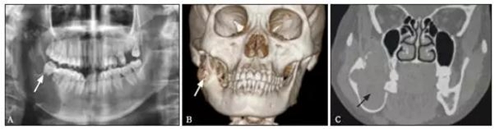

全景片、錐形束CT(cone beam computedtomography,CBCT)及螺旋CT結(jié)果提示:右側(cè)下頜骨體C6至下頜升支乙狀切跡區(qū)域可見一囊性病損,與正常骨邊界清楚,中心密度均勻,內(nèi)可見大小不等的分隔,邊緣呈切跡狀改變,病變累及乙狀切跡和喙突,向頰舌側(cè)膨隆明顯,舌側(cè)骨密質(zhì)不連續(xù),頰側(cè)骨密質(zhì)外可見骨膜反應(yīng),C78牙根有吸收。右下頜骨頰舌側(cè)不連續(xù)(圖1)。

圖1 患者術(shù)前檢查

A:全景片(箭頭所指為牙齒截根樣吸收);

B:螺旋CT平掃(箭頭所指為病變突破骨組織);

C:CBCT(箭頭所指為病變位置)。

(2)輔助檢查結(jié)合全景片、CBCT及螺旋CT平掃,發(fā)現(xiàn)患者影像上具有典型的成釉細胞瘤征象:囊性病變范圍廣泛,累及下頜升支及下頜角,牙根呈截根樣吸收,大小不等的分隔,且未見明顯的下牙槽神經(jīng)管擴張。結(jié)合臨床,病變較罕見,對于術(shù)前診斷造成了一定的影響。